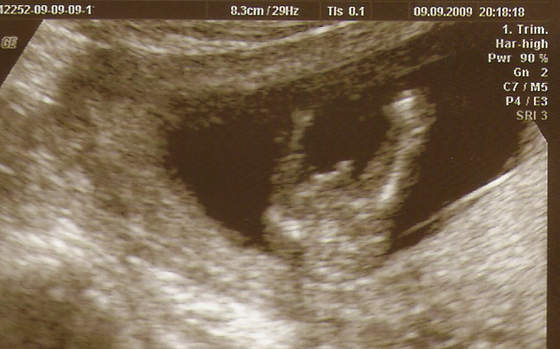

:-)No to przedstawiam Wam mojego Maluszka -

Zobacz załącznik 165063